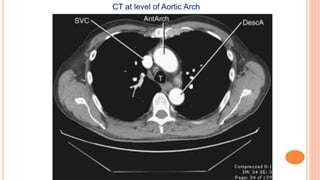

CT at level of Aortic Arch

CT at levelof Aortic Arch